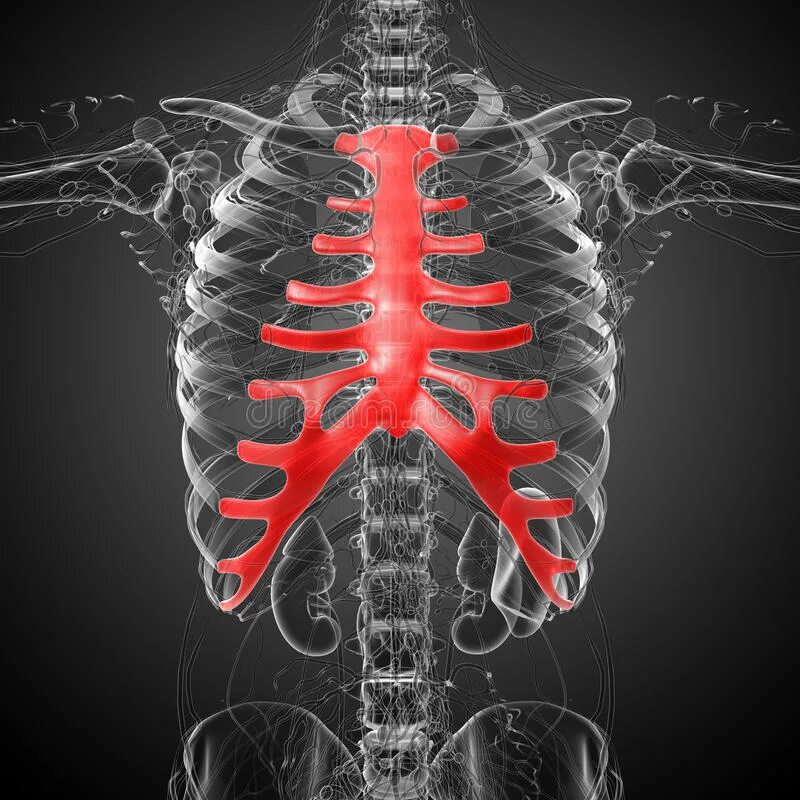

Множественные ребра